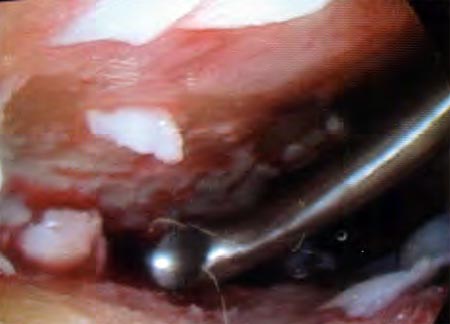

Se comienza por realizar la sinovectomía de la cámara anterior del tobillo con shaver, (Fig 3) lo cual mejora la visualización de las superficies articulares.

Figura 3: Shaver

Se realiza el cruentado de todas las superficies articulares con curetas rectas y curvas, incluyendo las goteras interna y externa. Generalmente cuando se comienza a realizar el desbridamiento, se va incrementando el espacio hacia la zona posterior, lo cual permite un completo denudamiento del cartílago de esta zona.

Cuando se completa la extirpación (Fig. 4) de todo el cartílago articular, se retira el manguito neumático y se comprueba el sangrado del hueso subcondral, luego se procede a la fijación del tobillo

Figura 4: Cureta